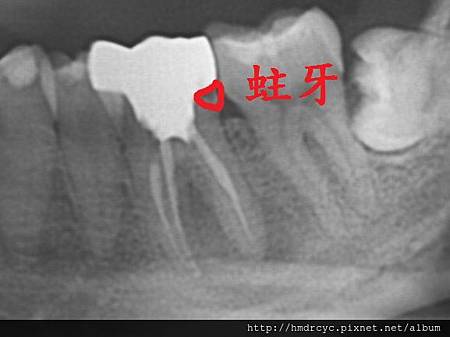

假牙必須利用X光片來更精確的判斷有沒有問題

在X光上面假牙是白色的影像

但X光片判讀困難 所以這部分必須仰賴醫師的專業

1. 蛀牙

蛀牙是常見的問題

臨床上可以在牙套邊緣勾到空隙

X光上則是一個黑色的蛀洞可以參考蛀牙範圍

X光通常會有1-2mm的誤差

所以實際上牙齒裡的洞會比影像大

只要牙套底下出現X光可以辨別的蛀洞

未來繼續蛀牙的速度會很快

牙套內的牙齒也會流失的很嚴重